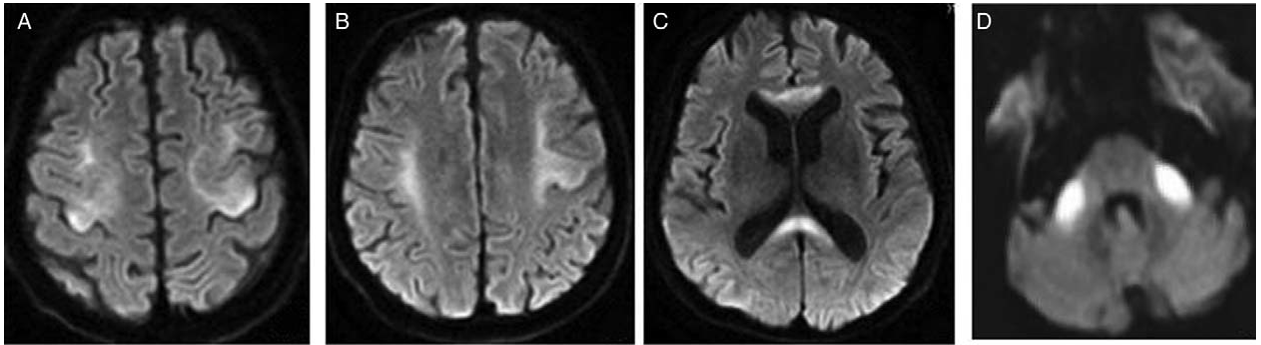

一、韦尼克脑病(Wernicke encephalopathy, WE)

该病主要由维生素B1(硫胺素)严重缺乏引起,长期酗酒导致的营养不良是常见原因,也可见于其他导致摄入不足或消耗过度的病理状态。临床常表现为精神意识障碍、眼球运动异常和行走不稳。早期诊断并及时补充维生素B1对改善病情至关重要。

影像表现(MRI):特征性表现为第三四脑室旁及导水管周围、乳头体、四叠体、丘脑等部位对称性长 T1 长 T2 异常信号影,T2-FLAIR 呈高信号,急性期可有强化。有些少见部位如小脑齿状核、桥脑被盖、红核、中脑顶盖、尾状核及大脑皮质也可见类似影像学改变,MRI 表现为病变部位对称性 T2WI 高信号影。

二、Marchiafava-Bignami病(Marchiafava-Bignami disease, MBD)

此病又称原发性胼胝体变性,是一种与慢性酒精中毒相关的罕见疾病,以胼胝体脱髓鞘和坏死为主要病理特征。临床上可分为急性、亚急性和慢性三种类型。急性起病者可迅速出现意识障碍、癫痫发作等严重症状;亚急性及慢性者多表现为言语障碍、肌张力增高、痴呆等。慢性型常出现大脑半球连接功能障碍(分离综合征)。

影像表现:急性期后胼胝体异常信号逐渐消退。慢性期表现为胼胝体萎缩伴局灶性长T1、T2信号,可能反映了进行性脱髓鞘、局灶性坏死和囊变。MBD患者也可出现胼胝体外受累,以皮质下白质最为多见,其他部位包括小脑中脚、内囊、前联合以及皮层。